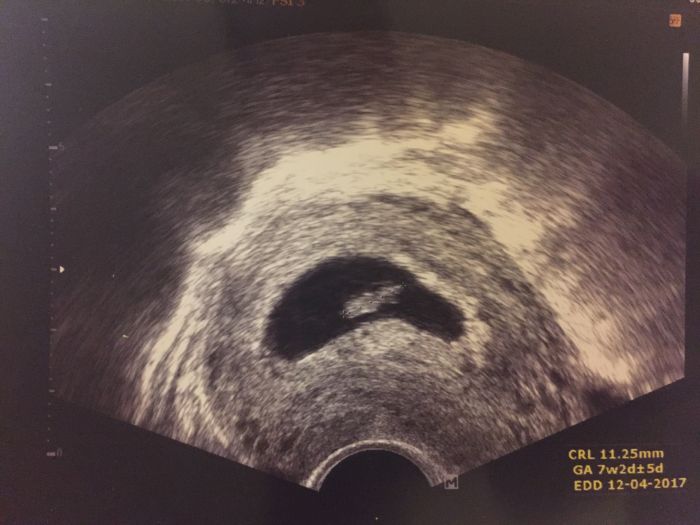

Ahooj :) tak jsem od dr zpátky doma. Kontrola mě tak dojala že jsem tam paní doktorce i zaslzela :)) vše v pořádku, těhotenství dokonce o týden starší dle utz s blikajicim srdíčkem :)) 7+2, termín cca 12.4.2017 a mamka říkala že takový termín měla když čekala mě, ale nakonec sem se narodila na konci března tak uvidíme jak to nakonec dopadne. Jestli nebude dárek k narozeninám :)) mám i foto ale je to ještě takový flíček :-D :-+

Juuuu, Baru, moc moc moc gratuluju!!!! Je to sice jen flicek, ale ten nejkrasnejsi ;-)